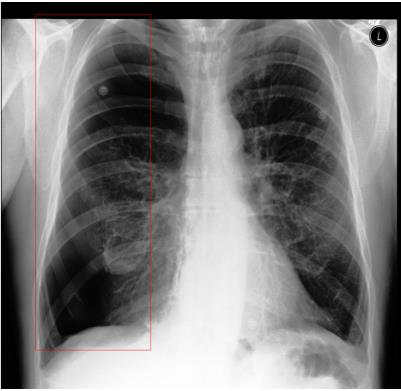

Traditional datasets for the radiological diagnosis tend to only provide the radiology image alongside the radiology report. However, radiology reading as performed by radiologists is a complex process, and information such as the radiologist's eye-fixations over the course of the reading has the potential to be an invaluable data source to learn from. Nonetheless, the collection of such data is expensive and time-consuming. This leads to the question of whether such data is worth the investment to collect. This paper utilizes the recently published Eye-Gaze dataset to perform an exhaustive study on the impact on performance and explainability of deep learning (DL) classification in the face of varying levels of input features, namely: radiology images, radiology report text, and radiologist eye-gaze data. We find that the best classification performance of X-ray images is achieved with a combination of radiology report free-text and radiology image, with the eye-gaze data providing no performance boost. Nonetheless, eye-gaze data serving as secondary ground truth alongside the class label results in highly explainable models that generate better attention maps compared to models trained to do classification and attention map generation without eye-gaze data.